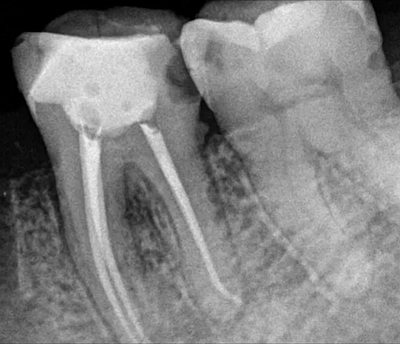

根管治療術(shù)又稱牙髓治療,是牙醫(yī)學中治療牙髓壞死和牙根感染的一種手術(shù)。該手術(shù)保留了牙齒,先是揭開髓室,頂敞開通路,用拔髓針拔除感染的牙髓。在用擴挫針擴凈根管壁,之后在根管內(nèi)封消炎藥,最后再用牙膠尖充填,手術(shù)繁瑣,一般要2-4次就診才能完成。隨著技術(shù)和材料的進步,活髓牙一次性根管治療術(shù),也在臨床應用。

根管治療步驟

1.開髓:即將患牙打開,暴露髓腔。

2.根管預備:通過不同器械在牙根里面切削清理擴大根管。

3.沖洗消毒:對患牙充分沖洗、消毒滅菌,然后封消毒液一周。

4.根管充填:一般放置人工無菌材料,封閉腔體。

5.對牙冠方向的缺損進行填充修復。一般整個治療過程需要就診兩到三次,根據(jù)患者情況而定。